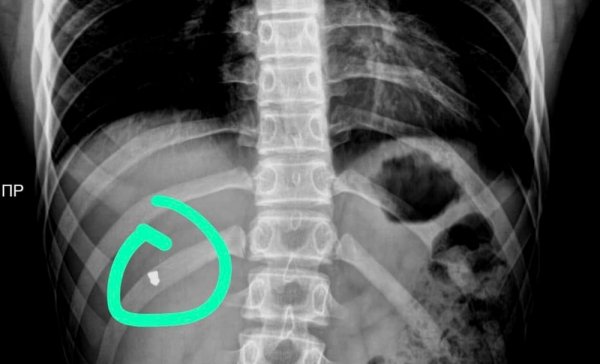

Пулю из груди подростка извлекли врачи в Актау

Подросток получил ранение по неосторожности в одном из аттракционов, сообщил общественник Азамат Сарсенбаев.

Фото предоставил Азамат Сарсенбаев

Как стало известно, в приёмный покой областной детской больницы 19 февраля был доставлен 16-летний подросток с пулевым ранением в грудную клетку.

По словам родителей, он по неосторожности получил ранение в тире парка «Акбота».

После полного обследования 22 февраля врачи провели сложнейшую операцию по извлечению пули от пневматического оружия из грудной клетки подростка. Для этого понадобилось эндоскопическое оборудование.

- Операция длилась примерно 40 минут. Благодаря современному оборудованию удалось провести сложную операцию без существенных проблем. В противном случае, как сетуют врачи, пришлось бы вскрывать грудную клетку, чтобы вытащить инородное тело, - рассказал Азамат Сарсенбаев.